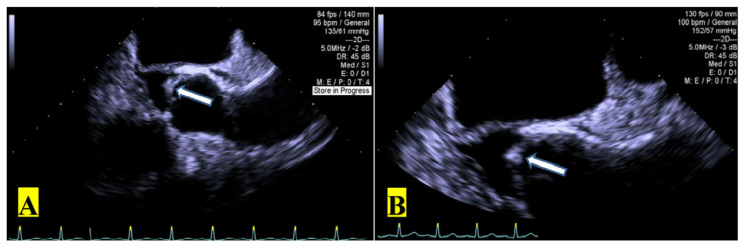

Aerococcus urinae is an alpha-hemolytic gram-positive catalase-negative coccus that typically causes urinary tract infections. It has been rarely implicated in other invasive infections such as endocarditis, bacteremia, peritonitis, meningitis, and vertebral osteomyelitis. There are approximately 50 reported cases of A. urinae infective endocarditis in literature. We present a rare case of a 64-year-old male who was found to have a urinary tract infection, bacteremia, and endocarditis caused by A. urinae.